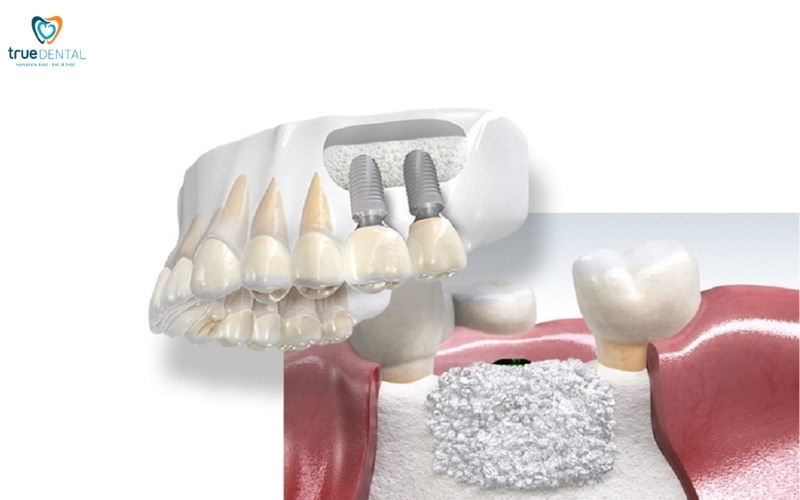

Ghép xương nhân tạo hoặc xương tự thân

Trong trường hợp răng đã mất lâu năm, xuất hiện tình trạng tiêu xương thì việc sử dụng vật liệu ghép xương là điều bắt buộc. Thực hiện kỹ thuật này sẽ giúp bạn không còn lo lắng cấy ghép implant có ảnh hưởng đến xoang hàm không.

- Ghép xương nhân tạo: Thường dùng các vật liệu tổng hợp hoặc có nguồn gốc động vật, có khả năng kích thích sự tái tạo xương tự nhiên của cơ thể. Vật liệu này sẽ dần được thay thế bằng xương mới của bệnh nhân.

- Ghép xương tự thân: Lấy xương từ một vị trí khác trên cơ thể (thường là cằm hoặc hông) của chính bệnh nhân. Xương tự thân có khả năng tích hợp và tái tạo tốt nhất.